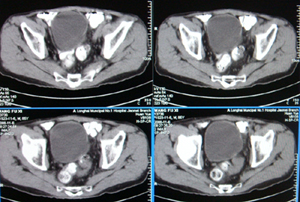

前列腺癌术后10余年,复查有无复发,请指教,图像做得不好,还望包涵

连续看还是前列腺的病变,考虑复发.

考虑前列腺癌复发.

结合病史考虑前列腺癌复发。

前列腺增大,向上突入膀胱内,结合病史考虑前列腺癌复发可能。

图像太小,左侧膀胱壁似见不规则突起,前列腺突入膀胱,建议膀胱镜检查及前列腺增强检查。